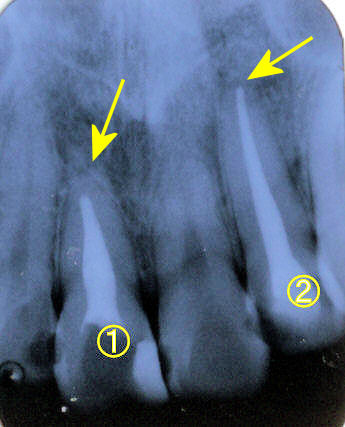

奥歯を入れたいのですが。

右下6番の歯を入れたいと来院されました。中学校の頃に6番の歯を抜かれておられたので7番の歯が前の方に倒れ込んで歯を作るスペースがありませんでした。ブリッジをするにしても倒れた歯を起こしておいた方が良いことをお話しました。今はミニインプラントがあるので簡単に起こすことができるようになりました。もちろん痛みもほとんどありません。その後、ブリッジよりは前の歯(5番)を削らないで済むならインプラントの方が良いということで6番にはインプラントを植立することになりました。 |